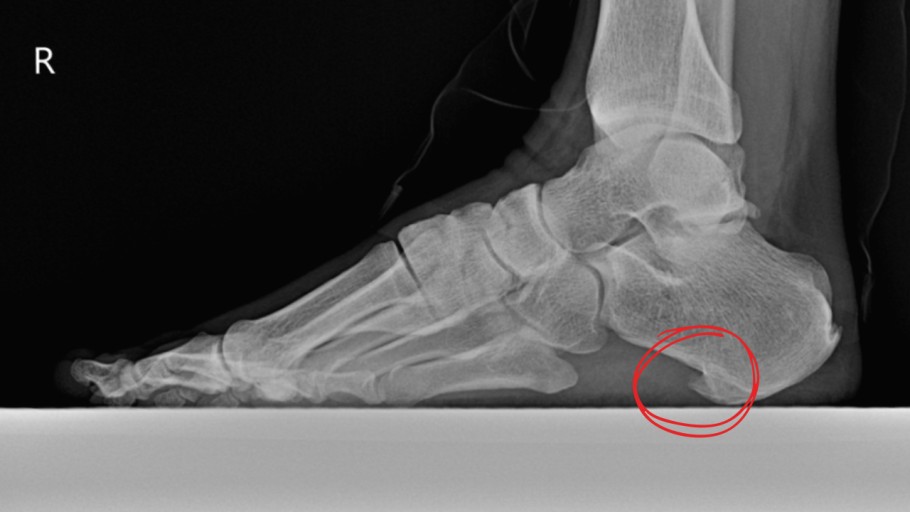

족저근막염은 발바닥을 지지해주는 근막에 염증이 생긴 상태로,

족저 근막염 증상 2. 뒤꿈치 통증

통증 부위는 대부분 발뒤꿈치 안쪽 또는 중앙 부위예요.